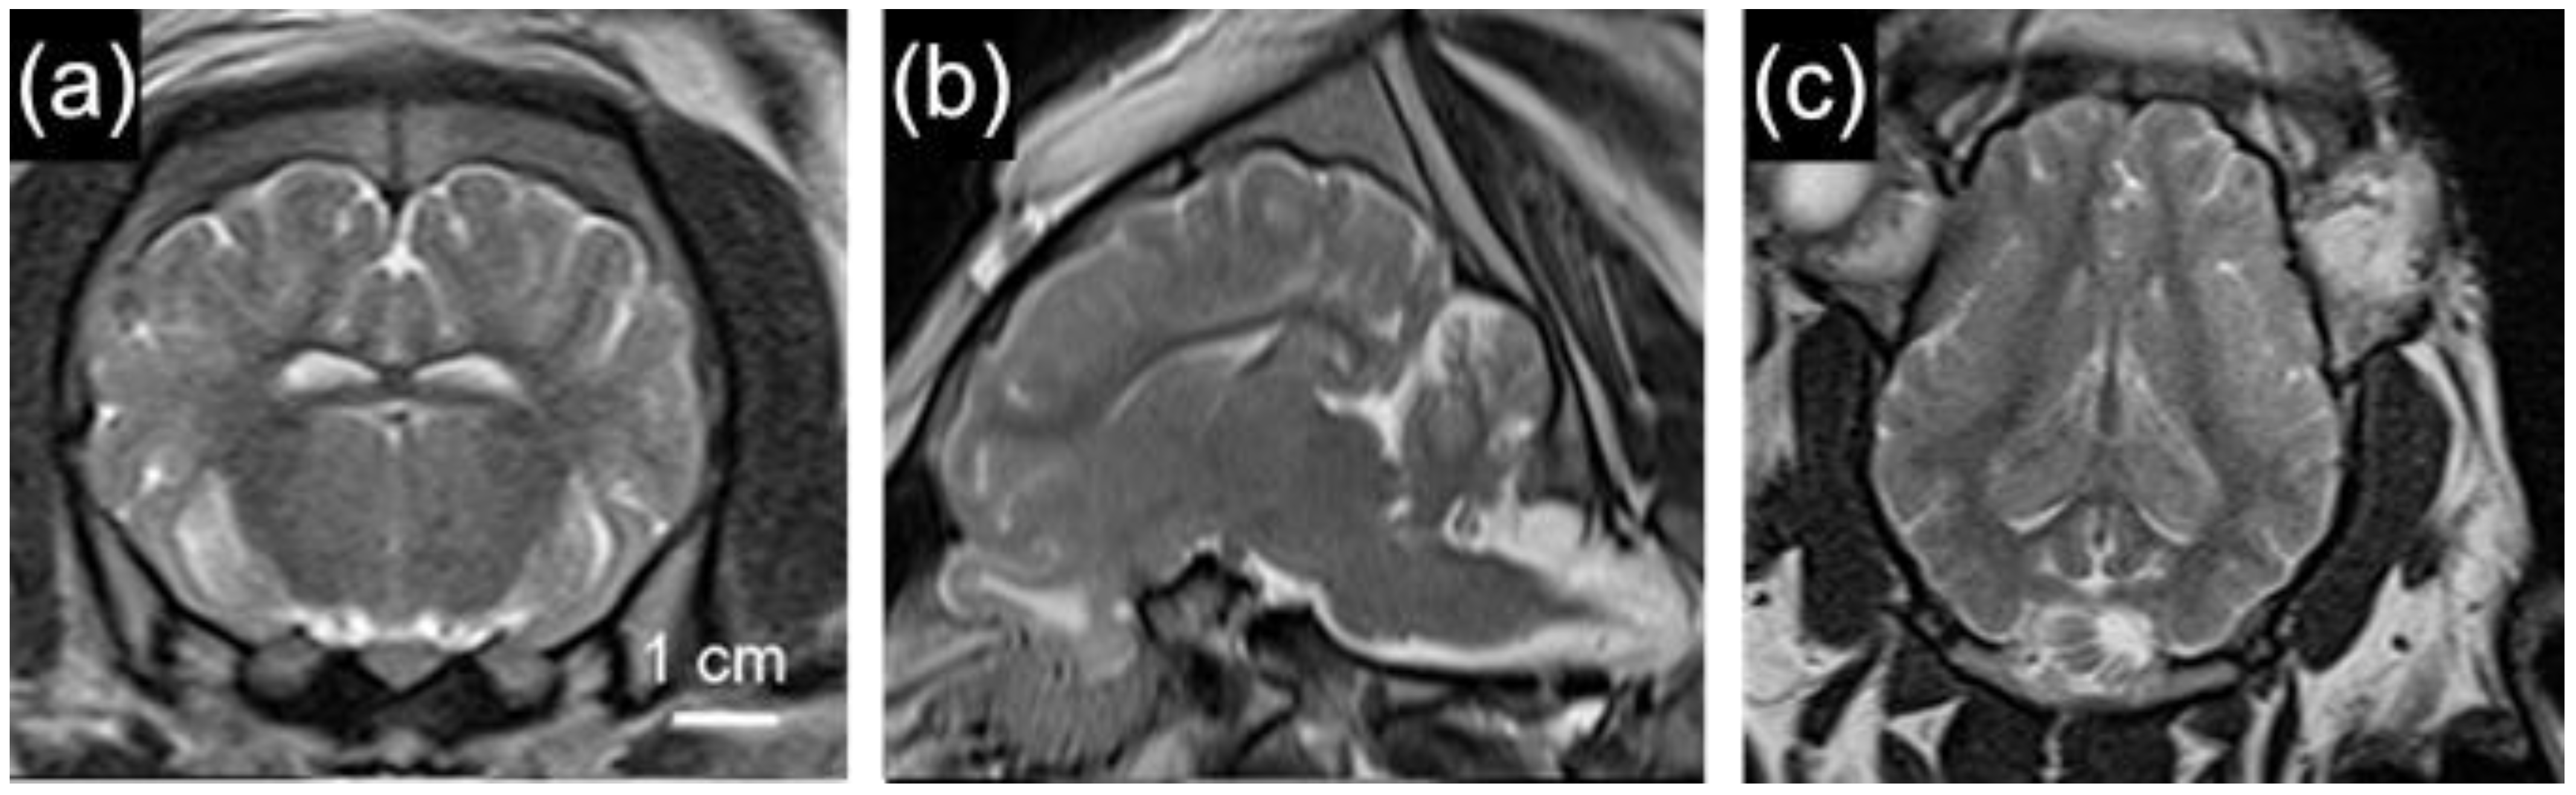

2.5.2. Neuroimaging

- Ryan, M.C.; Sherman, P.; Rowland, L.M.; Wijtenburg, S.A.; Acheson, A.; Fieremans, E.; Veraart, J.; Novikov, D.S.; Hong, L.E.; Sladky, J.; et al. Miniature pig model of human adolescent brain white matter development. J. Neurosci. Methods 2018, 296, 99–108. [Google Scholar] [CrossRef] [PubMed]

- Simchick, G.; Shen, A.; Campbell, B.; Park, H.J.; West, F.D.; Zhao, Q. Pig Brains Have Homologous Resting-State Networks with Human Brains. Brain Connect. 2019, 9, 566–579. [Google Scholar] [CrossRef]

- Lee, J.K.; Liu, D.; Jiang, D.; Kulikowicz, E.; Tekes, A.; Liu, P.; Qin, Q.; Koehler, R.C.; Aggarwal, M.; Zhang, J.; et al. Fractional anisotropy from diffusion tensor imaging correlates with acute astrocyte and myelin swelling in neonatal swine models of excitotoxic and hypoxic-ischemic brain injury. J. Comp. Neurol. 2021, 529, 2750–2770. [Google Scholar] [CrossRef]